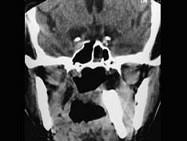

问题 67岁男性患者,咽喉部异物感3年余,从小经常出现咽喉部疼痛伴发热,行X线及CT检查如图所示,请选择正确的描述和结论 ( )

选项 A、右侧扁桃体出血 B、右侧扁桃体肿瘤 C、CT示右侧下颌骨内侧咽旁间隙见条形致密影 D、右侧扁桃体结石 E、侧位示与下颌骨部分重叠的条形致密影

答案 CDE